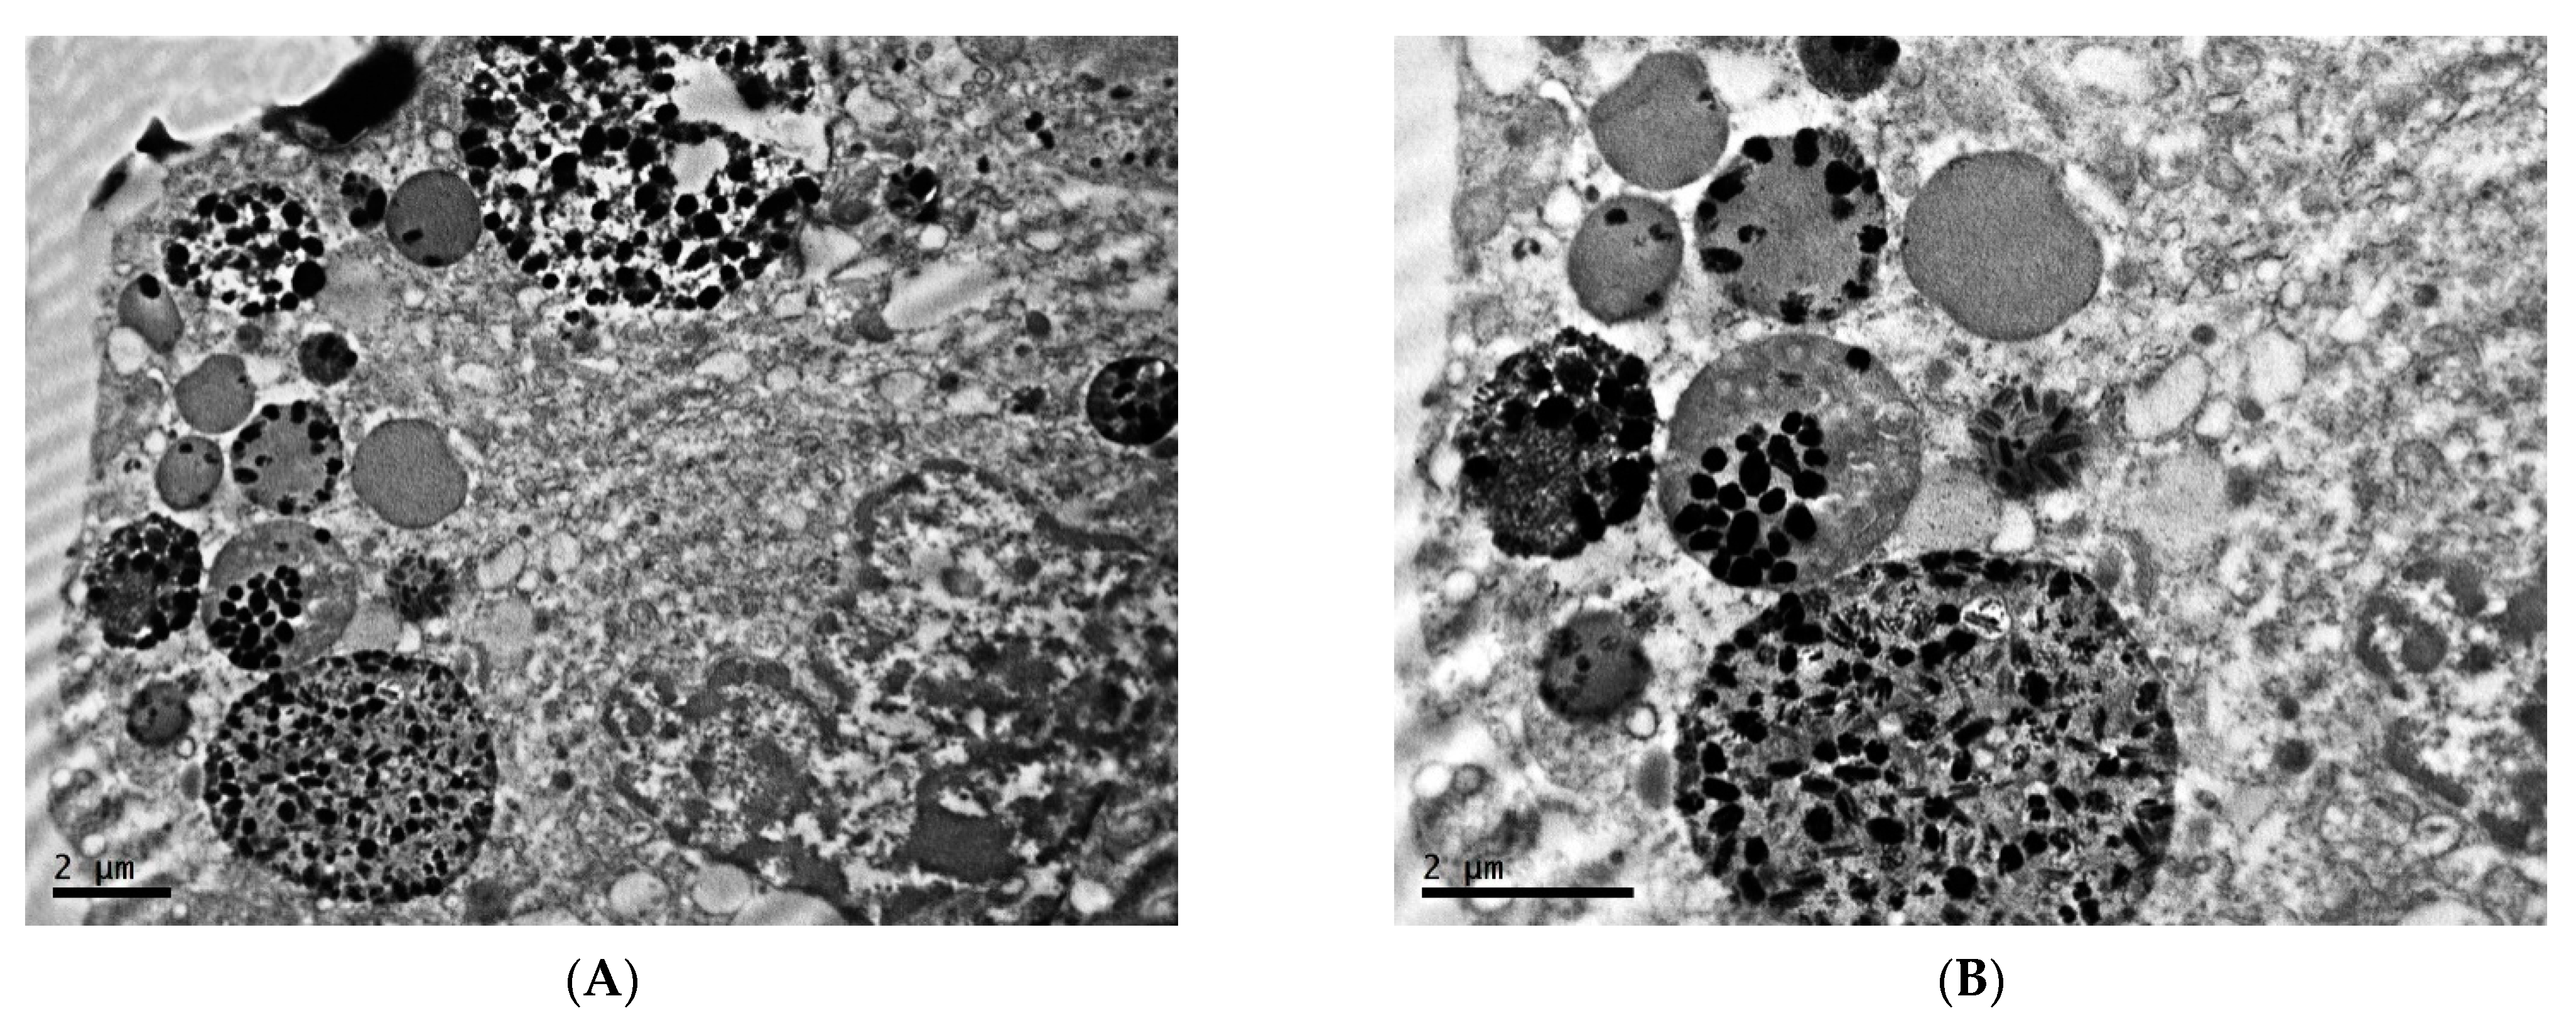

2.1. Ultrastructure of Transplantable Malignant Melanoma B16 in Conditions of Fixed Light Regime